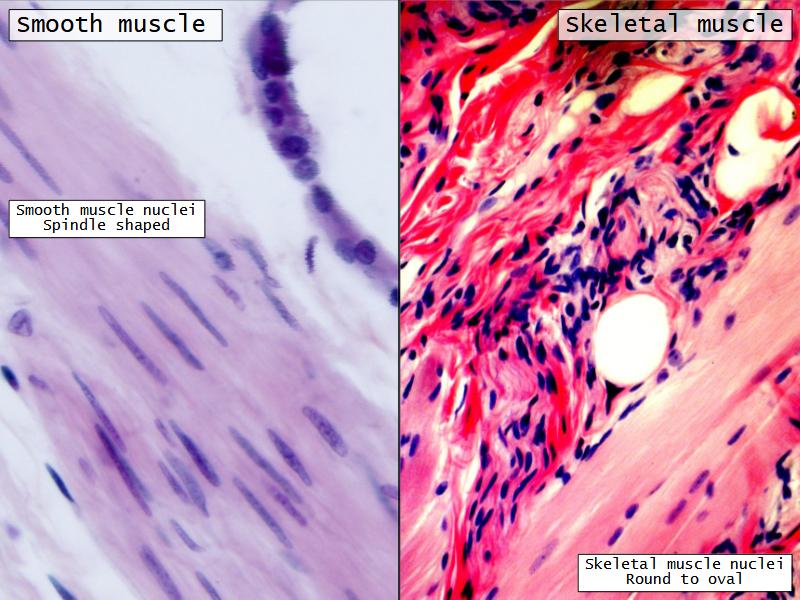

Name three types of contractile cells.

Bronchi - Transitions

- Bronchioles

- Smooth muscle REPLACE cartilage

- Ciliated columnar > Ciliated cuboidal

- Smooth muscle

- Ciliated cuboidal epithelium